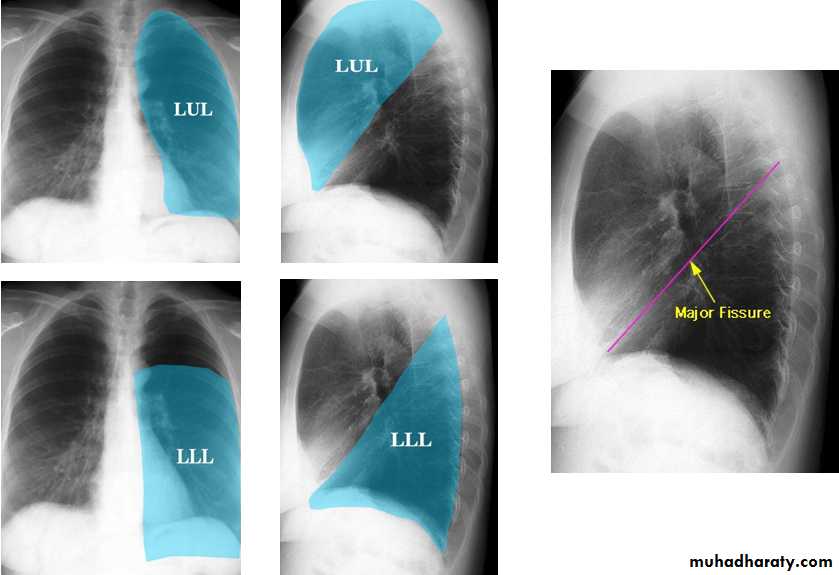

The lung

The left lung has two lobes and the right has three

Each lobe has its own pleural covering

The horizontal fissure (right) is often seen on a normal frontal view

The oblique fissures are often seen on a normal lateral view .

Lobes and fissures

This cut-out of a lateral chest x-ray shows the positions of the lobes of the right lung

On the left the oblique fissure is in a similar position but there is usually no horizontal fissure, and so there are only two lobes on the left.

Radiologic anatomy of the RT lung lobes

Radiologic anatomy of the LT lung lobes